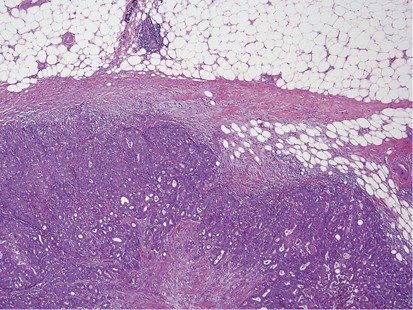

Glass slides were available for review in 53 out of 85 (62%) cases. These slides included 28 core biopsies and 30 excisions (5 cases with both cores and excisions). Seven cases involved lymph nodes only (6 axillary and 1 intramammary). The remaining 46 cases all involved the breast. Mammary lymphatic only involvement, without stromal invasion, occurred in 7% (3/46) of the cases. Certain recurrent histological features were identified, including a well-circumscribed nodule (74%, 34/46), often surrounded by a fibrous pseudocapsule (52%, 24/46) with varying thickness (Figure 1) and absence of an in situ mammary carcinoma. Interestingly, in the great majority of the tumors, lymphovascular invasion was notably absent (87%, 40/46). Tumoral calcifications were observed in non-mammary metastases of serous carcinoma type that were psammomatous in nature (75%, 6/8) (Figure 2), including two cases that involved lymph nodes.